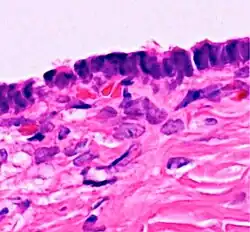

Serous cystadenoma | Histopathology of serous cystadenoma, with admixed scattered ciliated cells. This case closely resembles normal surface endometrial epithelium of the uterus | Category: Histopathology of ovarian serous cystadenoma | Ovarian cystadenoma |

![]() |